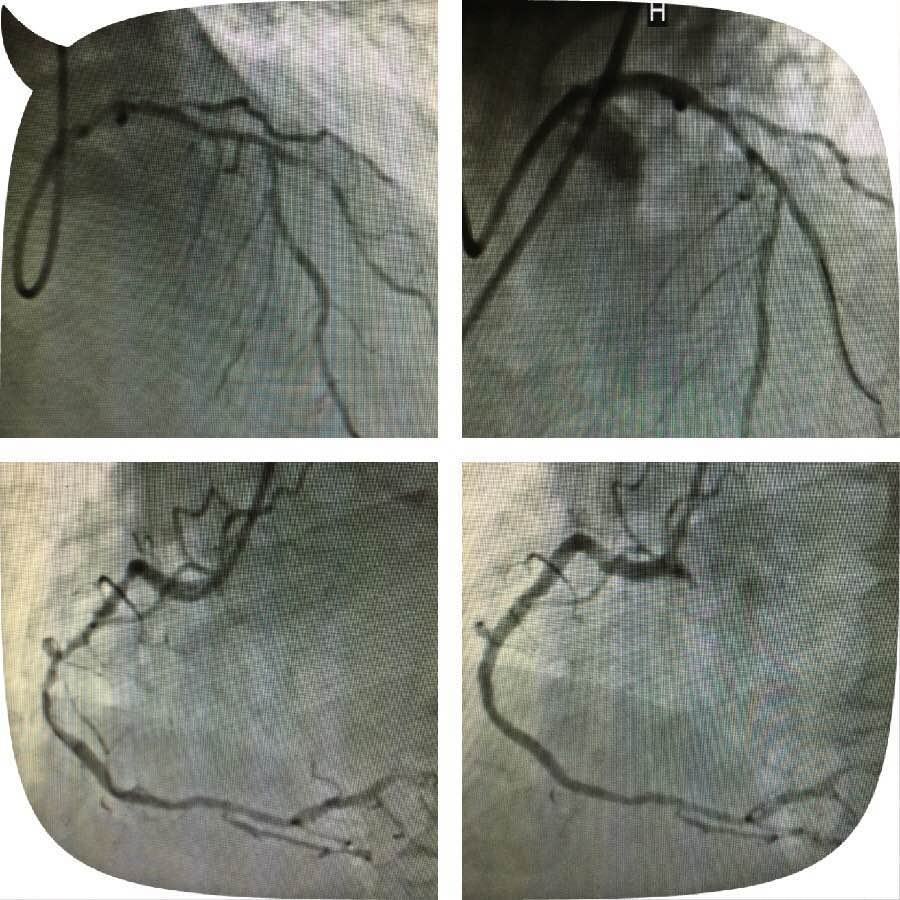

啄木鸟 心血管病医院应用切割球囊成功完成1例高危冠脉左主干钙化狭窄病变介入

原来,这位老人突发心脏病被送到啄木鸟 心五病区,入院后心电图示非ST段抬高心肌梗死,急诊行冠状动脉造影检查发现左主干钙化严重狭窄,合并右冠脉钙化严重狭窄病变,死亡风险极高。考虑患者病变复杂,贸然行左主干介入治疗风险极高,针对此患者特殊情况,心血管病医院组织专家进行缜密讨论,并与患者及家属充分沟通交流后,制定了血运重建的合理治疗方案。首先完成患者右冠脉钙化并严重狭窄病变的介入治疗,再次应用切割球囊行左主干严重钙化狭窄病变和对角支严重狭窄病变的介入治疗。

实施右冠严重狭窄长病变的介入治疗一周后,患者病情稍有缓解,经心血管病医院专家的缜密讨论,拟行切割球囊治疗患者的左主干钙化并严重狭窄病变,手术由心五病区郭瑄主任及陆艳副主任医师实施。术中如预期情况一样,经普通球囊反复扩张后,左主干的狭窄仍显得“纹丝不动”,患者出现胸痛症状,手术时间延长一分,患者手术风险增加十分,这时应用切割球囊就是关键的利器。手术成功!术中患者各项生命体征平稳,安返病房。